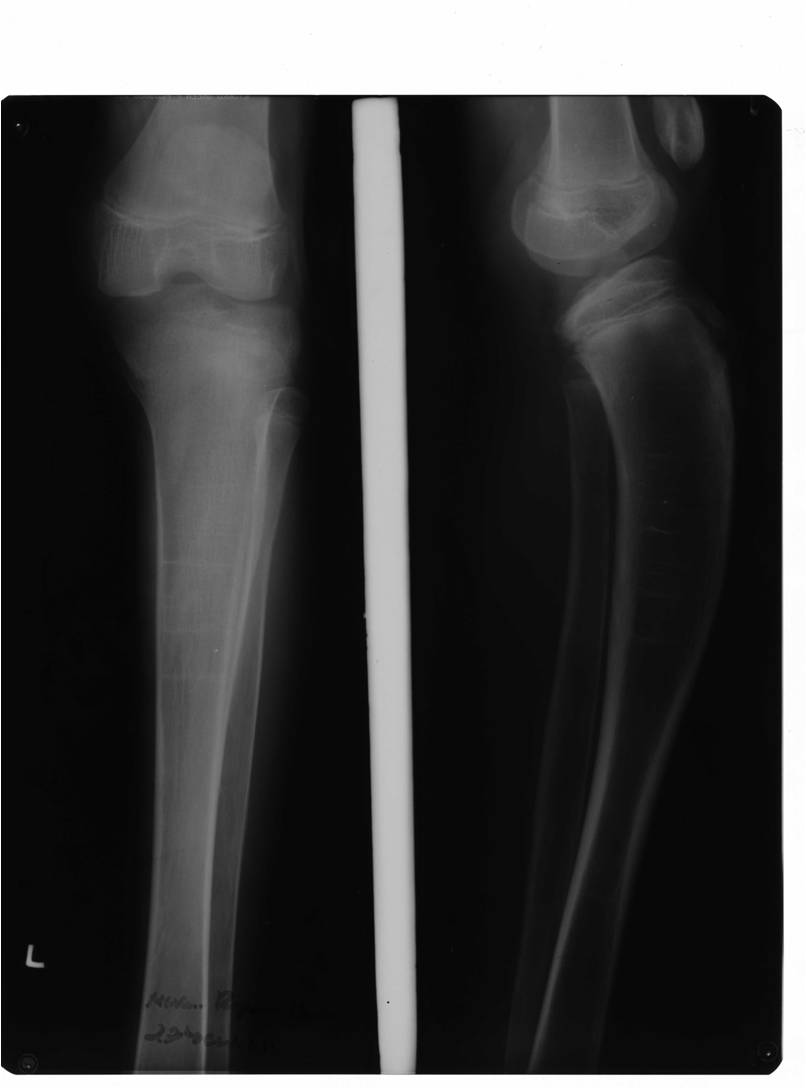

Pyles Dysplasia2